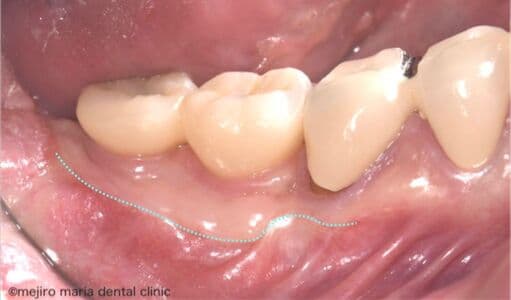

インプラントを守るための歯茎の移植(FGG)

インプラント周囲の歯茎が薄く、付着歯肉が不足していると、ブラッシング時に歯茎が動いて汚れが残りやすくなり、インプラント周囲炎のリスクが高まります。本症例では、遊離歯肉移植術(FGG)を行い、硬く安定した付着歯肉を再建しました。強い歯茎を得ることで、清掃性を高め、長期的にインプラントを健康に保つことを目指した症例です。

治療内容 遊離歯肉移植術(FGG)

治療期間 3ヶ月(移植した歯茎が落ち着くまで)

治療回数 1回(他、抜糸や経過観察を除く)

治療費用 137,500円(税込)

症例から言えること

インプラントを長く維持するためには、人工歯そのものよりも、周囲の歯肉環境が重要です。FGGにより付着歯肉を十分に確保することで、外的刺激に強く、清掃性に優れた環境を整えることができます。インプラント周囲の歯茎が薄い、磨きにくいと感じる方には、歯周形成外科的アプローチが有効な治療となります。